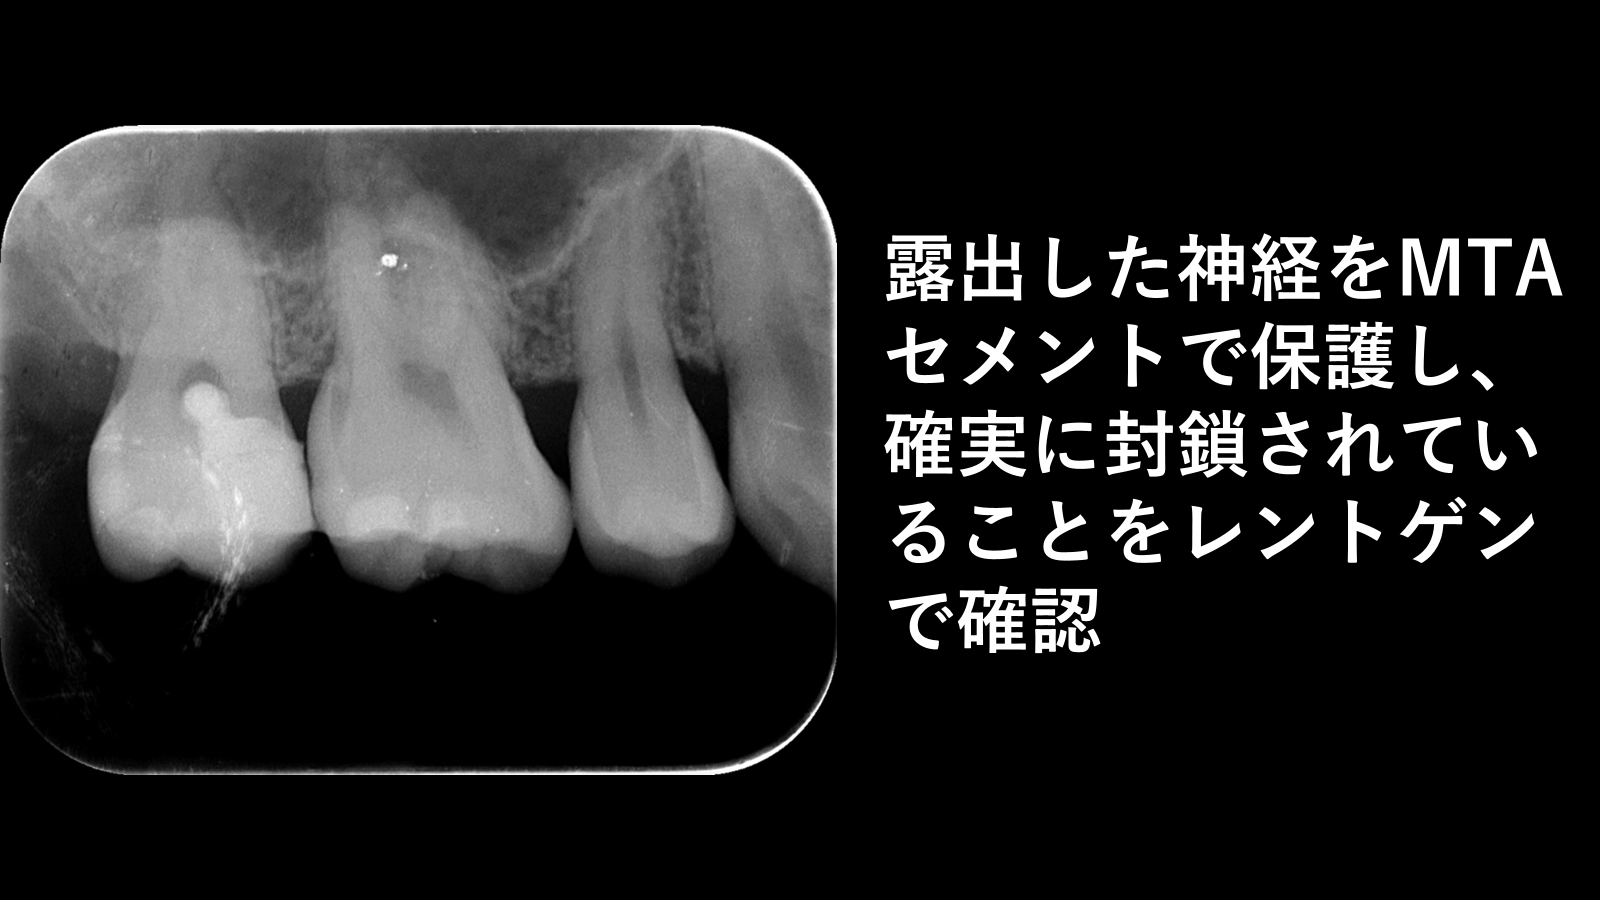

奥歯に大きな虫歯を認めた症例です。 虫歯が歯の内部まで進行しており、虫歯を除去した際に歯の神経(歯髄)の露出を認めました。 通常、このようなケースでは神経を取り除く「根管治療」が選択されることが多いですが、本症例では歯髄の炎症が可逆的と判断されたため、神経を保存する歯髄温存療法を行いました。 露出した歯髄を適切に処置した後、MTAセメントを用いて神経を保護・封鎖し、その上からセラミックにて修復を行いました。 処置後のレントゲン写真にて、MTAセメントが確実に封鎖されていることを確認しています。 歯の神経を残すことで、歯の寿命を長く保つことにつながる可能性があります。

その後、セラミックよる直接修復を行い、処置後のデンタルX線写真にて封鎖状態を確認しました。